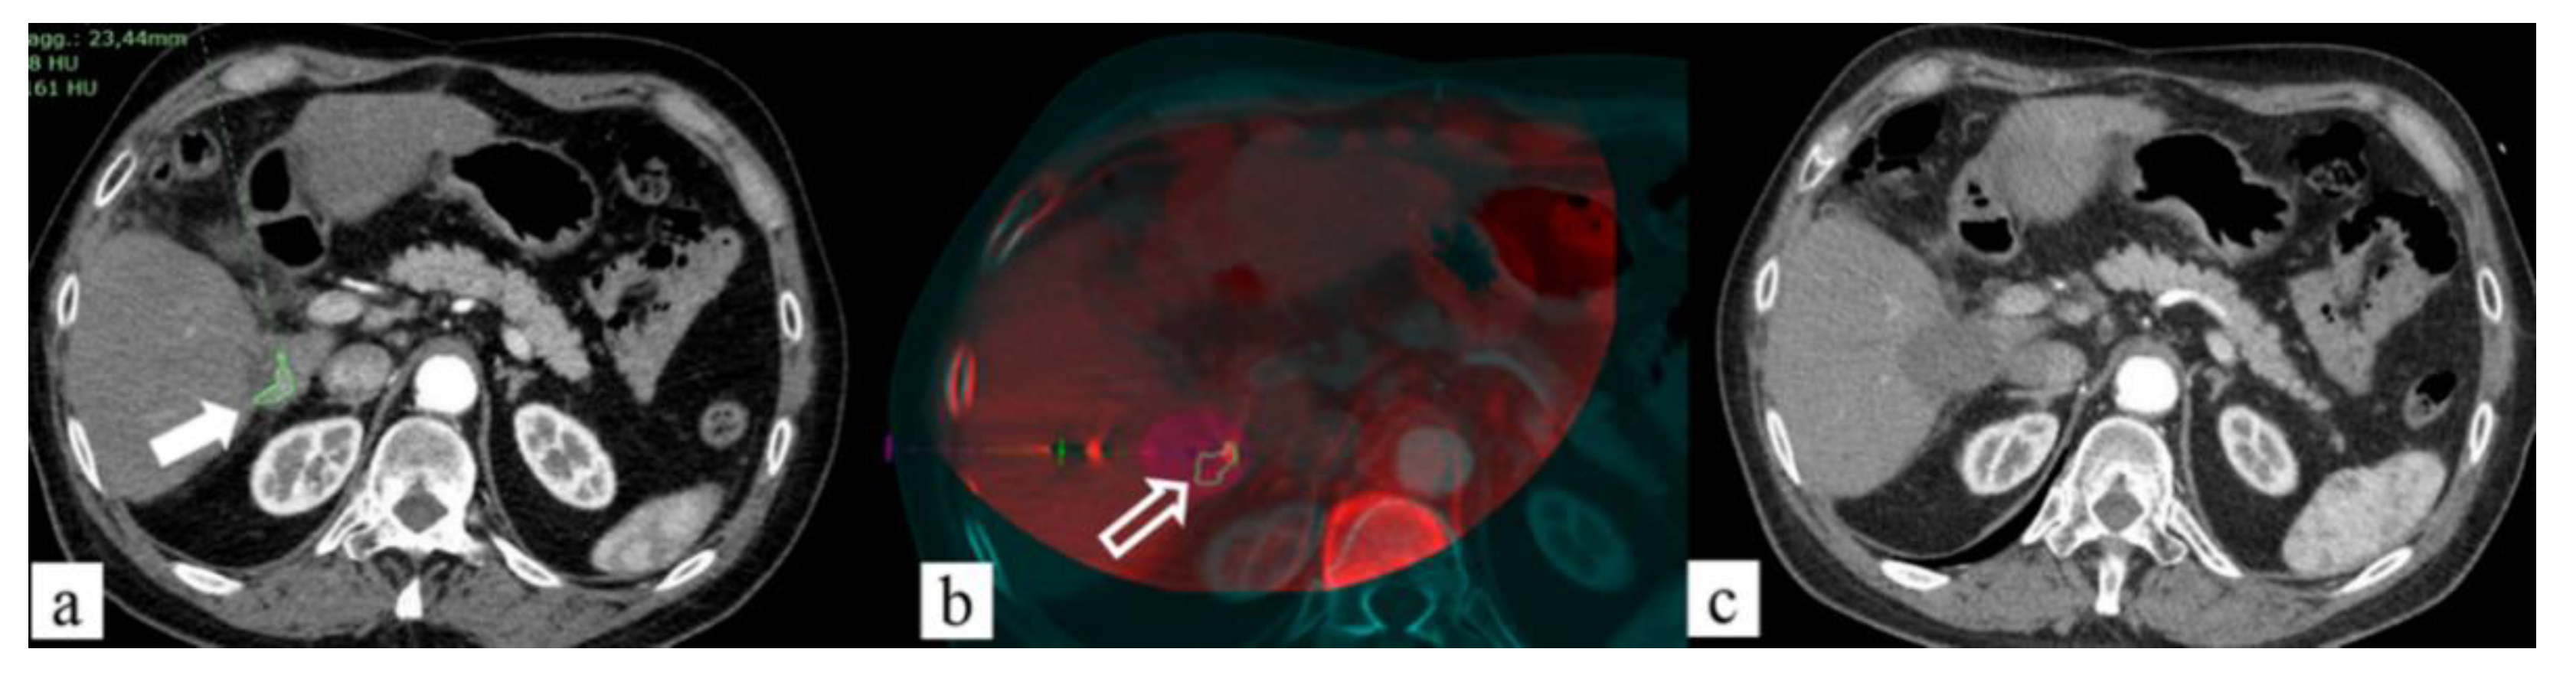

- Li, J.; Li, Z.; Jiao, D.-C.; Si, G.; Zhou, X.; Li, Y.; Liu, J.; Han, X. Clinical Outcomes After Selective Renal Artery Embolization Combined With DynaCT-Guided Microwave Ablation for T1a Renal-Cell Carcinoma: Case Series. Clin. Genitourin. Cancer 2021, 19, e1–e5. [Google Scholar] [CrossRef] [PubMed]

- Li, Z.; Jiao, D.; Han, X.; Si, G.; Li, Y.; Liu, J.; Xu, Y.; Zheng, B.; Zhang, X. Transcatheter Arterial Chemoembolization Combined with Simultaneous DynaCT-Guided Microwave Ablation in the Treatment of Small Hepatocellular Carcinoma. Cancer Imaging 2020, 20, 13. [Google Scholar] [CrossRef] [Green Version]